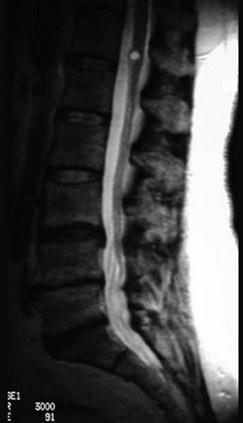

问题 哪些不是髓外硬膜下肿瘤(如图所示)的特点()

选项 A.分离性感觉障碍 B.脊髓半侧损害综合征 C.感觉和运动障碍自上而下发展 D.感觉和运动障碍自下而上发展 E.根性疼痛

答案 AC